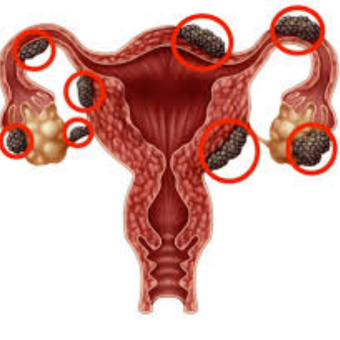

Ovarian Cysts

Endometriosis